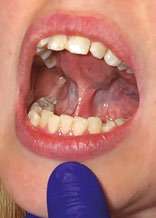

Intraoral examination revealed narrow, flattened dental arches and posterior overjet (Figure 2A-D). Teeth crowding was present in both jaws, along with a midline discrepancy (Figure 2A-D). The tongue appeared wide, with scalloped edges (see the right image in Figure 5A). A thick, very tight, restrictive lingual frenal attachment was noted (Figure 2D and 2E).

After a mixture of Lidocaine 2% with 1:100,000 epinephrine was administered by local infiltration, the LightScalpel laser frenuloplasty was performed to release both the maxillary labial and lingual restrictions. LightScalpel® CO2 laser (LightScalpel, LLC, Bothell, WA) with 0.25 mm focal spot size laser handpiece was utilized, delivering 2 watts repeat, non-SuperPulse laser beam gated at 50% duty cycle at 20 Hz (average power to the tissue was 1 watt). For efficient incision, in order to create tension and ensure that the larger vasculature is pushed away from the surgical site, the patient was asked to put her tongue in the “suction-cup” position (Figure 3A). (OMT prior to a functional frenum release is necessary in order to tone the lingual muscles and ensure the patient’s ability to create and maintain tongue suction.) The dentist applied gentle traction with her fingers while performing the release (Figure 3B). When performed with scissors, this technique requires the use of a hemostat to clamp smaller blood vessels prior to sharp dissection. With the CO2 laser no hemostat is typically necessary, because smaller vasculature (under 0.5 mm) is efficiently coagulated by the 10,600 nm laser wavelength.

The laser nozzle was held 1-2 mm away from the target tissue (Figure 3B) and moved in a steady hand speed for controlled depth of incision motion. The myofunctional therapist was present throughout the entire procedure. In the course of the procedure, the dentist stopped several times, while the therapist assessed the remaining tension and the tongue mobility. First, after the dentist removed the most apparent, superficial fascial restriction, the myofunctional therapist measured the basic range of motion (ROM), palpated the tongue, using gentle experienced touch and trying to locate the presence of tightness or restriction. The patient was asked to lift, extend the tongue, and put it in the “suction-cup” position. The patient was already able to protrude and elevate her tongue better, but there was still tension and the dentist proceeded with a deeper release. At this point, no cutting was done; instead, blunt dissection was used to divide deep fascia – this technique helps the natural release, almost “melting”, of fascia. After that, the patient reported the sensation of the front neck tension alleviation. By the end of the procedure, the myofunctional therapist felt a release of the tension in the mid-portion of the tongue, where a big knot had been detected during preoperative examination. Finally, the last bit of tension detected by the myofunctional therapist was addressed by extending the incision vertically, upward, with the laser (Figure 3E).